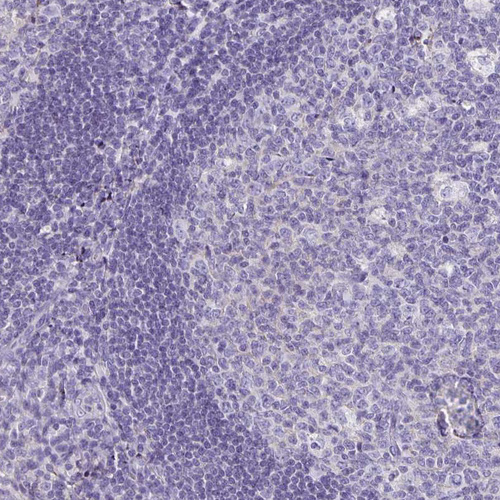

Immunohistochemistry analysis in human pancreas and tonsil tissues using HPA002550 antibody. Corresponding TTR RNA-seq data are presented for the same tissues.